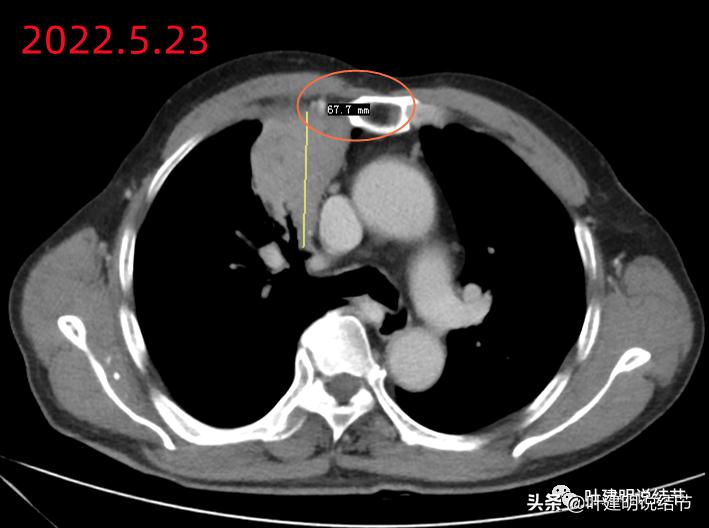

到此,相关检查都没有肺癌的依据。我们在抗炎治疗约9天后予以复查胸部CT平扫,看病灶有没有变化。本来是考虑如果没有缩小好转,也先间隔4-6周再复查下再决定是否重新活检或手术切除。不想短短几天,居然病灶有了明显缩小:

前后10来天,居然效果惊人的好!那肯定要考虑非肿瘤性的了。